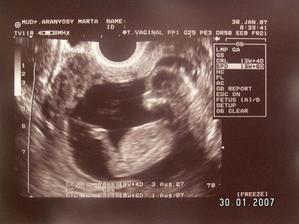

SRPŇÁTKA 2007 - fotky UTZ

album věnované mimískům, které se narodí v srpnu 2007 a jejich maminkám ze "Společného termínu SRPEN"